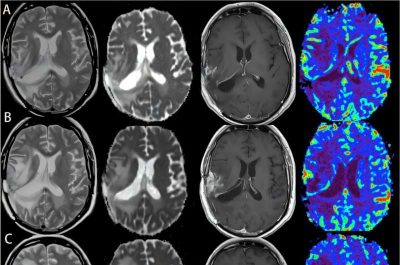

Glioblastomi-immagini: un caso di glioblastoma recidivato durante l’immunoterapia. Crediti: Yan Li et al, CC BY 4.0

Il Dott. Behnan e i suoi colleghi hanno utilizzato tecniche di imaging avanzate su topi che avevano sviluppato due diversi tipi di glioblastomi. Hanno scoperto che i tumori causavano l’erosione delle ossa del cranio, soprattutto lungo le suture di fusione delle ossa .

Tali erosioni sembrano essere peculiari del glioblastoma e di altri tumori intracranici maligni, poiché non si verificano in caso di ictus, altri tipi di danno cerebrale o persino altri tumori sistemici. Le immagini di tomografia computerizzata ( TC ) di pazienti con glioblastoma hanno rivelato che le riduzioni dello spessore del cranio erano presenti nelle stesse aree anatomiche dei topi.

Si è scoperto che le erosioni craniche nei topi avevano aumentato il numero e il diametro dei canali cranio-osso. I ricercatori hanno ipotizzato che questi canali potessero consentire al glioblastoma di trasmettere segnali al midollo cranico, modificandone profondamente il sistema immunitario.